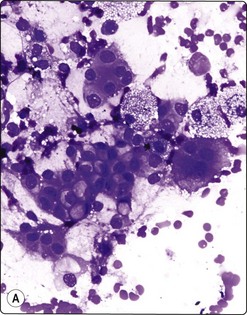

Pseudocyst (Fig. 11.5)

These non-neoplastic cysts are the most commonly encountered pancreatic cysts. Being fluid collections occurring in post-pancreatitic states, they are not true cysts and as such are lined by granulation tissue, not by epithelium. Aspiration yields copious turbid watery fluid which contains debris, occasional inflammatory cells including histiocytes, possible fibroblasts and bile, and perhaps rare fragments of epithelial tissue from the surrounding gland. Raised enzyme levels, e.g. amylase and lipase, and low or absent tumor marker levels are found in the aspirated cyst fluid. The fluid is nonmucinous, but may demonstrate background fibrinous strands. Should the aspirate appear purulent, it should be submitted for culture to confirm secondary infection.

image image

Fig. 11.5 Pancreatic pseudocyst

(A) Mainly debris, inflammatory cells and macrophages; a few clusters of degenerating epithelial cells (Pap, IP); (B) These degenerating epithelial cells may be interpreted as atypical and are a pitfall leading to false-positive diagnoses (MGG, HP).